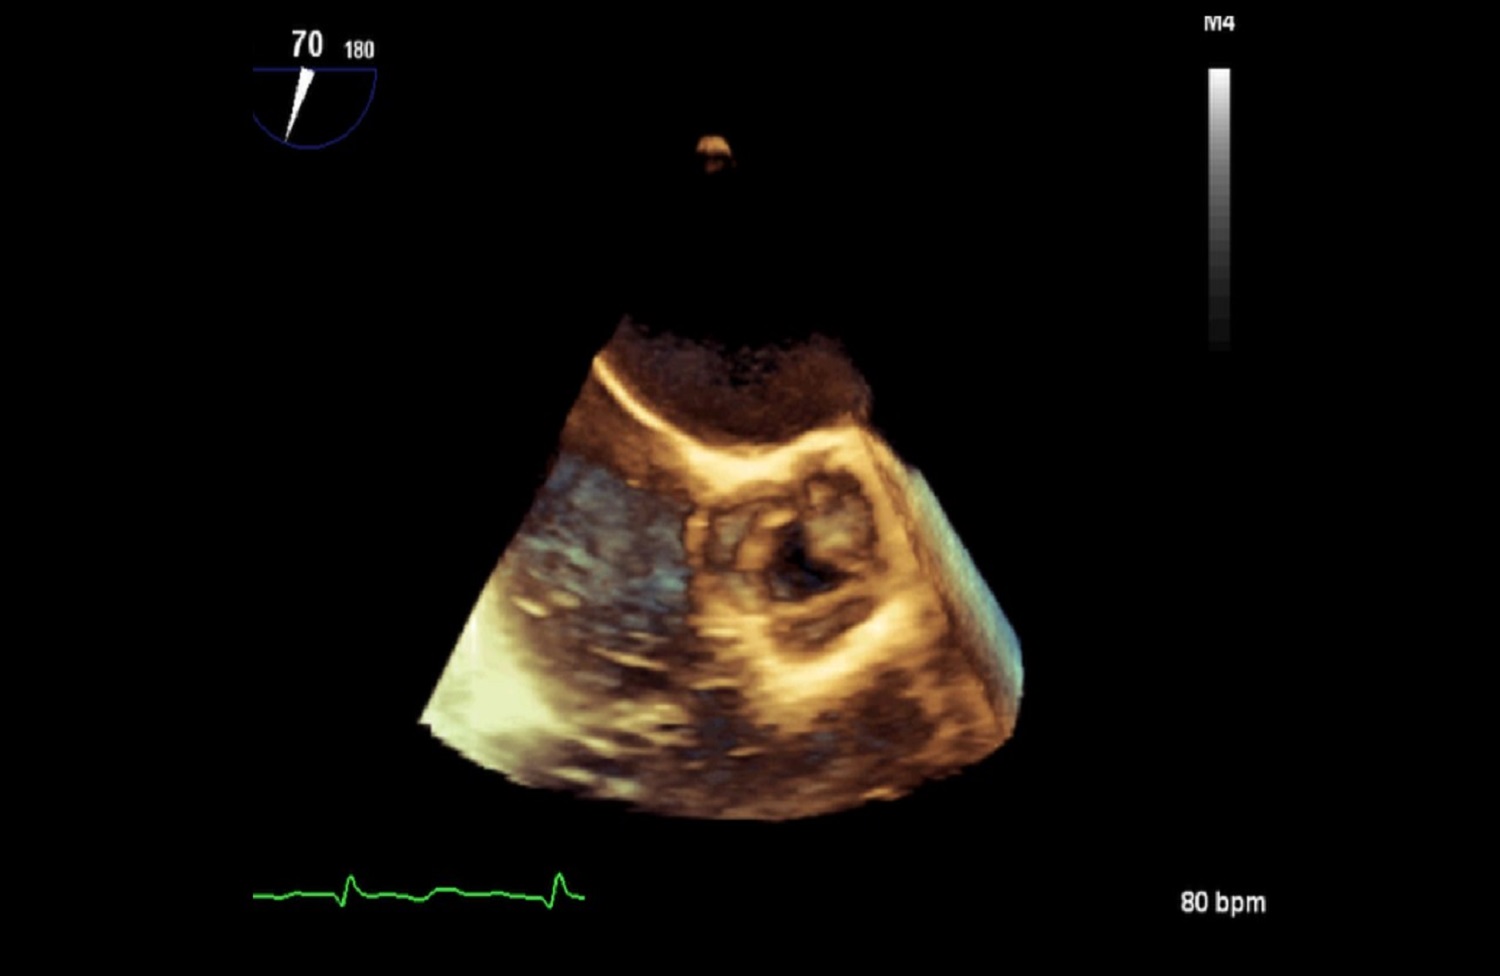

Pracownia Echokardiografii

Pracownia Echokardiograficzna Kliniki posiada Akredytację Klasy C (najwyższy poziom referencyjny) przyznaną przez Zarząd Sekcji Echokardiografii Polskiego Towarzystwa Kardiologicznego. W ciągu roku wykonywanych jest tu łącznie ponad 3600 badań echokardiograficznych przezklatkowych, przezprzełykowych i prób z dobutaminą.

Pracownia wyposażona jest w 2 aparaty przenośne: Philips CX 50 oraz Vivid Q.

W Pracowni badani są pacjenci hospitalizowani w oddziałach Kliniki oraz we wszystkich pozostałych Klinikach Szpitala Klinicznego Dzieciątka Jezus, a także pacjenci ambulatoryjni kierowani z Poradni Kardiologicznej, Nadciśnienia Tętniczego, Przeciwzakrzepowej, Transplantacyjnej i Nefrologicznej Szpitala. Pracownia ukierunkowana jest na diagnostykę zatorowości płucnej, nadciśnienia płucnego, wad zastawkowych, infekcyjnego zapalenia wsierdzia oraz dysfunkcji lewej komory.

Dzięki wykwalifikowanemu personelowi i nowoczesnemu sprzętowi w Klinice wykonywane są również przezskórne zabiegi zamknięcia ubytków przegrody międzyprzedsionkowej typu II oraz drożnego otworu owalnego, pod kontrolą echokardiografii dwu – i trójwymiarowej.

Na podstawie badań z zastosowaniem przezprzełykowej echokardiografii trójwymiarowej w pracowni kwalifikuje się również pacjentów z ciężką niedomykalnością mitralną w mechanizmie wypadania płatka mitralnego do nowatorskich zabiegów małoinwazyjnej przezkoniuszkowej naprawy zastawki bez użycia krążenia pozaustrojowego. Efektem współpracy z Oddziałem Kardiochirurgii Szpitala Medicover była możliwość monitorowania echokardiograficznego przezprzełykowego dwóch pierwszych w Polsce zabiegów naprawy zastawki mitralnej z użyciem robota chirurgicznego da Vinci.